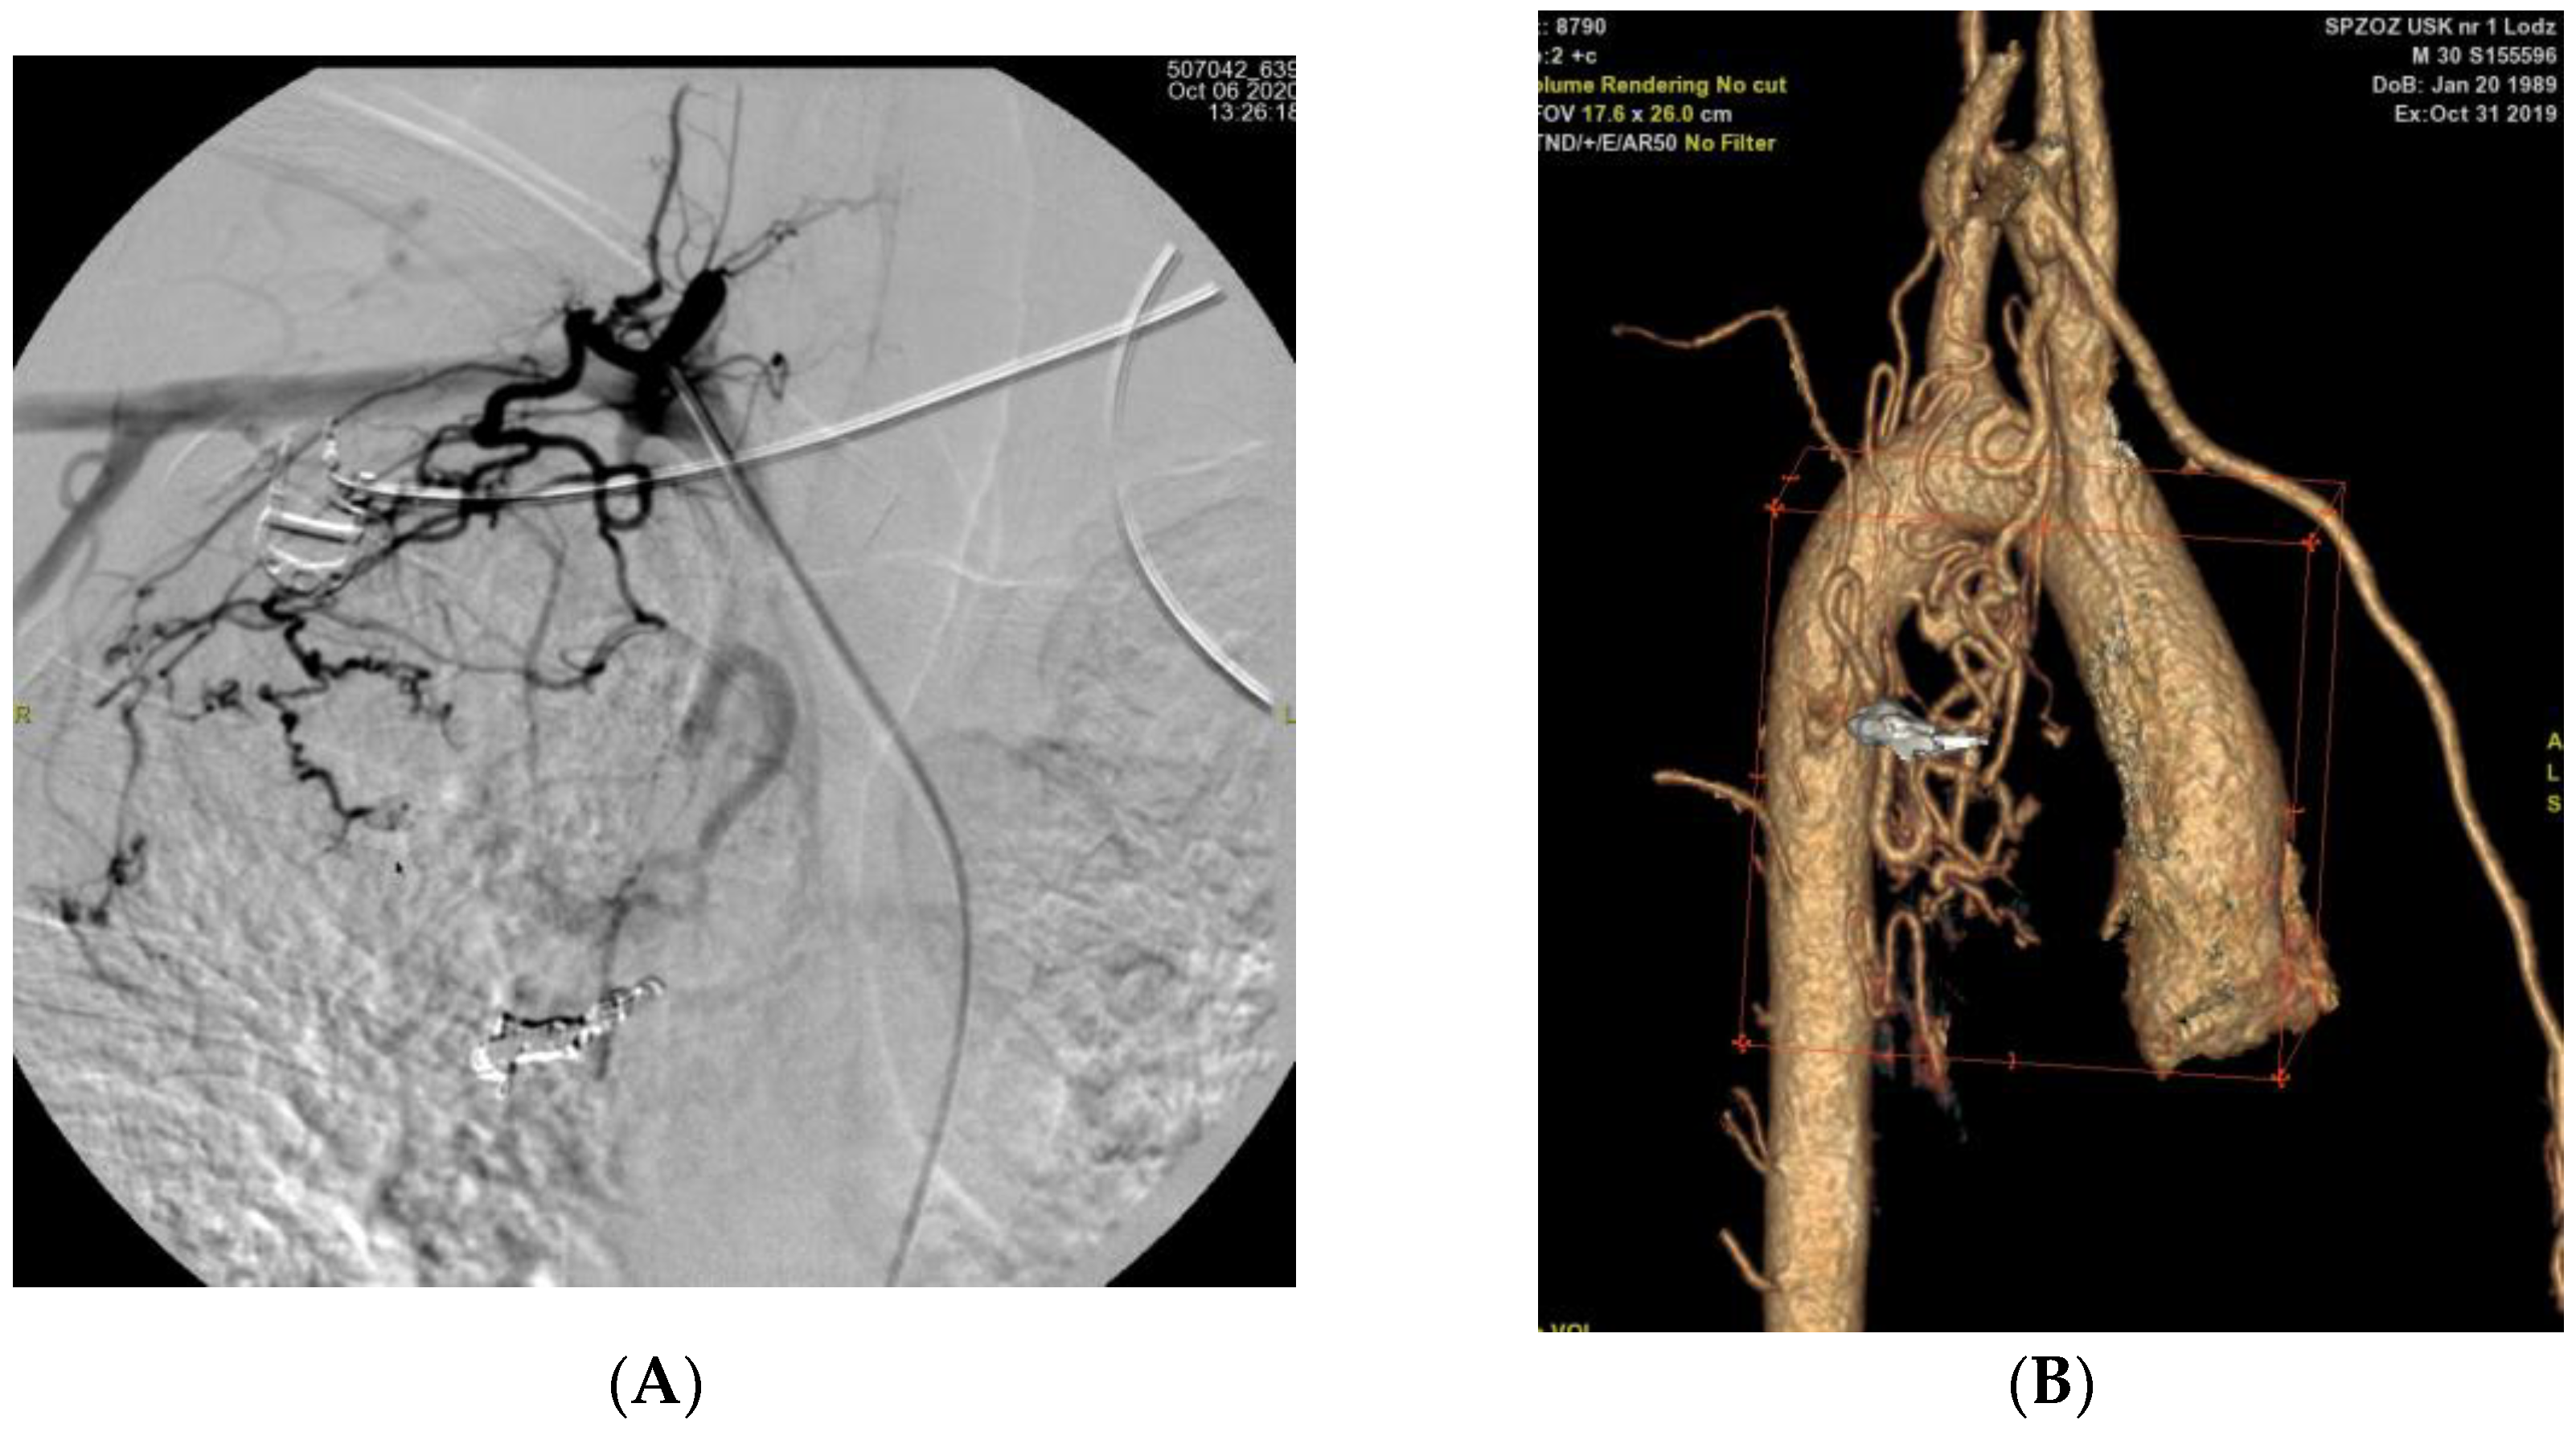

| P03 | LIMA dilated to 3.1 mm; L BA to 3.3 mm; L inferior phrenic a. to 3.1 mm Post-inflammatory changes bilaterally Fibrotic transformation of LL | L Th12 aortic branch (phrenic a.) | Yes |

| P03 | Branch of the aorta at T12 (likely left inferior phrenic artery) | First | Coil |